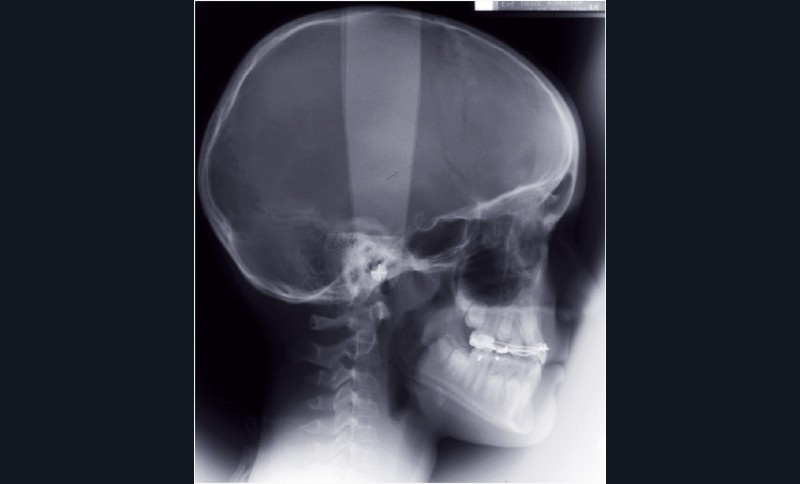

Cette étape de traitement a permis la normalisation des rapports cranio-maxillo-mandibulaires (fig. 10).

Elle est suivie d’une phase de surveillance triannuelle dans l’attente de l’évolution dentaire.